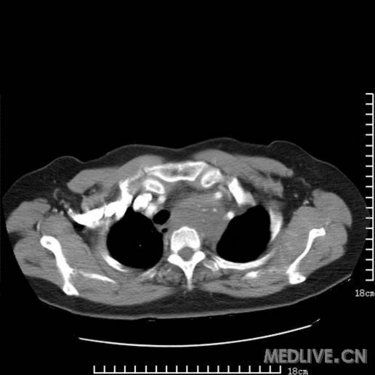

是胸腺瘤?畸胎瘤?高手支招_影像医学和核医学